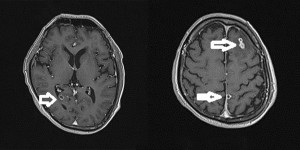

TS.BS Trần Huy Thọ, Phó giám đốc Bệnh viện Đặng Văn Ngữ cho biết, kết quả xét nghiệm ELISA của bệnh nhân dương tính với ấu trùng sán dây lợn. Chụp cộng hưởng từ sọ não thấy khối tổn thương ký sinh tại vùng não của anh N do ấu trùng sán dây lợn.

“Hiện tượng đau đầu, co giật của bệnh nhân là do bệnh ấu trùng sán dây lợn ký sinh trên não gây nên”, bác sĩ Thọ nói.